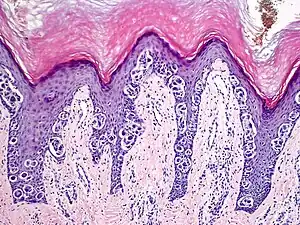

An acral nevus is a cutaneous condition of the palms, soles, fingers, or toes (peripheral body parts), characterized by a skin lesion that is usually macular or only slightly elevated, and may display a uniform brown or dark brown color, often with linear striations.[1]: 1726

They are brown to dark brown in color and have linear streaks of darker pigmentation. Size is usually 7 mm or less, oval or spindle shaped, and well-demarcated. They become stable after an initial growth phase, and the number of lesions also decreases; a new lesion in middle-aged or elderly people should raise suspicion of acral lentiginous melanoma.